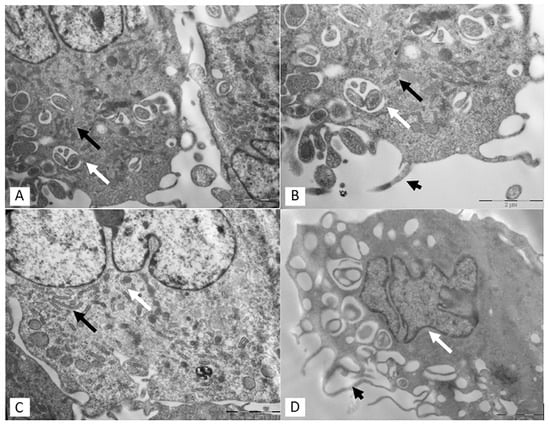

3.2. Transmission Electron Microscopy (TEM)